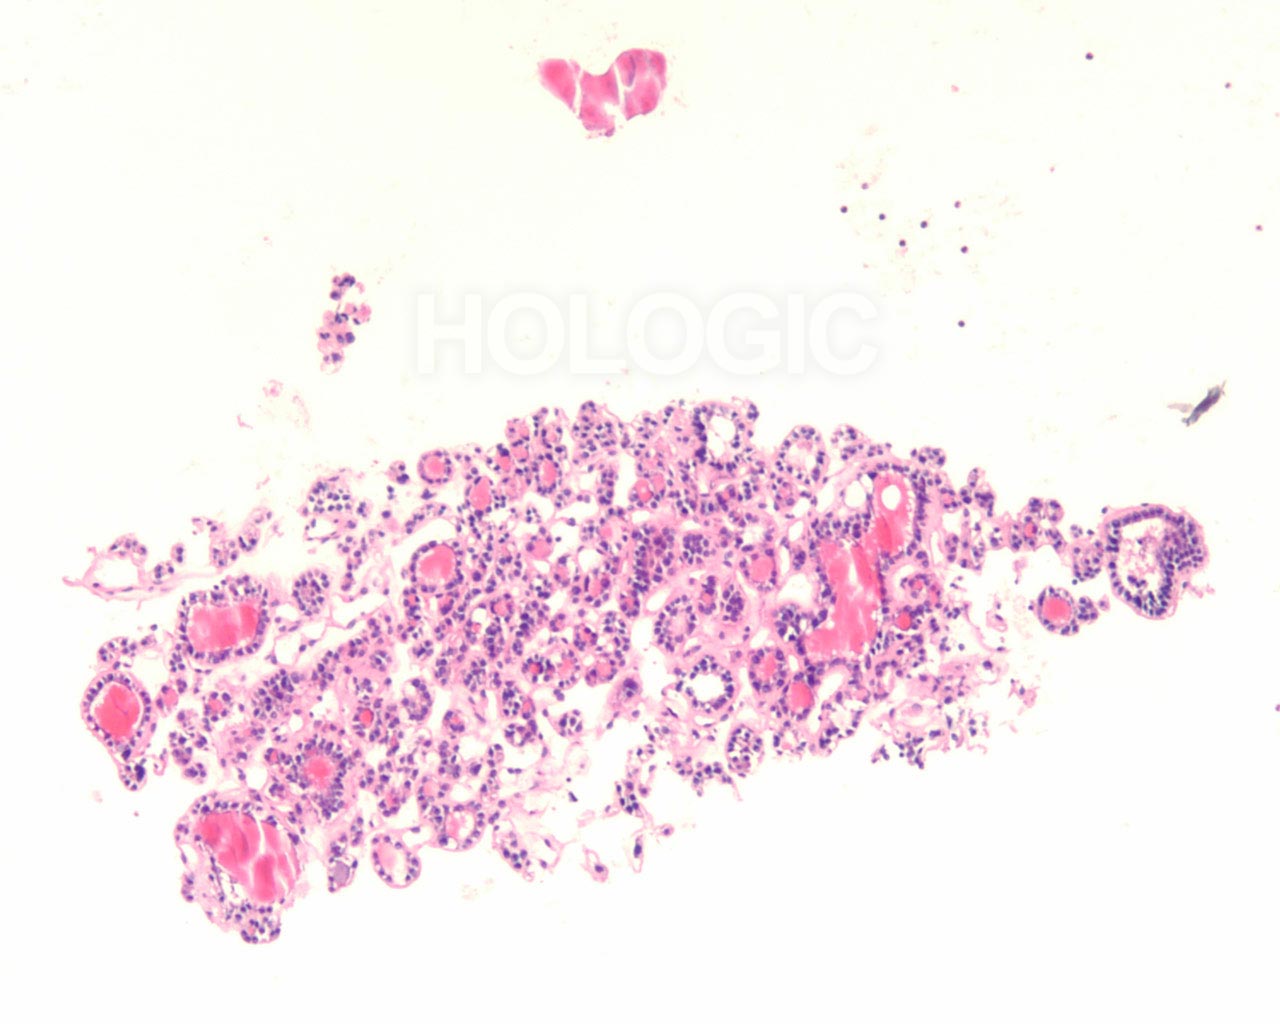

Met celblokken kan de afmeting van de follikel beoordeeld worden op een manier die een aanvulling vormt op de ThinPrep-glaasjes. Om een follikel als groot aan te merken, moeten de folliculaire cellen over een tamelijke grote afstand 2-dimensionaal georganiseerd zijn; als de follikels klein zijn, bevinden de cellen zich niet in een brede 2-dimensionale, platte laag. Het is verrassend moeilijk het eens te worden over de definitie van ‘macrofolliculair’ [9]. Acht tot 10 folliculaire celdiameters lijkt een redelijke definitie voor de macrofolliculaire colloïd fragmenten [9], of voor de diameter van platte, 2-dimensionele macrofolliculaire lagen. In weefselcoupes die loodrecht op een macrofolliculaire groep zijn gesneden, zien de macrofollikels eruit als een lineaire ordening van ten minste 8 folliculaire cellen. Als de sectie in het vlak van een macrofolliculaire groep snijdt, kan men gemakkelijk een solide uitziende celmassa tegenkomen die analoog is aan een weefselcoupe die tangentieel recht door de ductale cellaag snijdt in een schildklier biopsie. Net als pathologen een dergelijke tangentiële coupe kunnen herkennen en kunnen onderscheiden van ductale hyperplasie, kan men een tangentiële coupe door macrofolliculaire groepen herkennen. Dit wordt hieronder geïllustreerd. Microfollikels hebben per definitie een hoge ratio tussen de cellen en het colloïd en de cellen kunnen niet in een brede 2-dimensionele laag liggen. In celblokcoupes vertonen microfollikels geen lange lineaire organisatie van cellen. Renshaw et al. vonden een significante grijze zone onder experts in het onderscheid tussen microfolliculaire en macrofolliculaire groeperingen op cytologische preparaten [9].Een van de belangrijkste grijze gebieden betreft het probleem van folliculaire cellen die artefactueel op elkaar zijn gestapeld. Deze artefactuele stapeling van cellen lijkt gemakkelijker te diagnosticeren in weefselcoupes. Een ander probleemgebied betreft die gevallen waarin microfollikels en macrofollikels door elkaar zijn gemengd. Het is ons en anderen opgevallen dat benigne stromanodulen vaak plat cytoplasma vertonen in de cellen van de microfollikels. De robuustere cellen van een folliculair neoplasma tonen vaak veelal kubusvormige of zelfs cilindrische, folliculaire cellen die de microfollikels bekleden [7]. Deze kenmerken zijn duidelijk in celblokcoupes en worden hieronder geïllustreerd.

Benigne folliculaire nodulen vertonen vaak een bijmenging van cytologisch verschillende typen folliculaire cellen. De follikels van folliculaire neoplasmen zijn meestal uniform van aard. Hoewel het uiterlijk van de follikels in een cytologisch preparaat van groep tot groep kan worden vergeleken, kan deze benadering van het beoordelen van de klonaliteit soms moeilijk zijn. Het kan bijvoorbeeld onmogelijk zijn om te weten of de FNA-naald buiten het neoplasma monsters heeft genomen. Met celblokken kunnen de morfologische kenmerken van waarlijk aangrenzende follikels over een bereik van enkele honderden microns geëvalueerd worden, zoals hieronder geïllustreerd wordt.